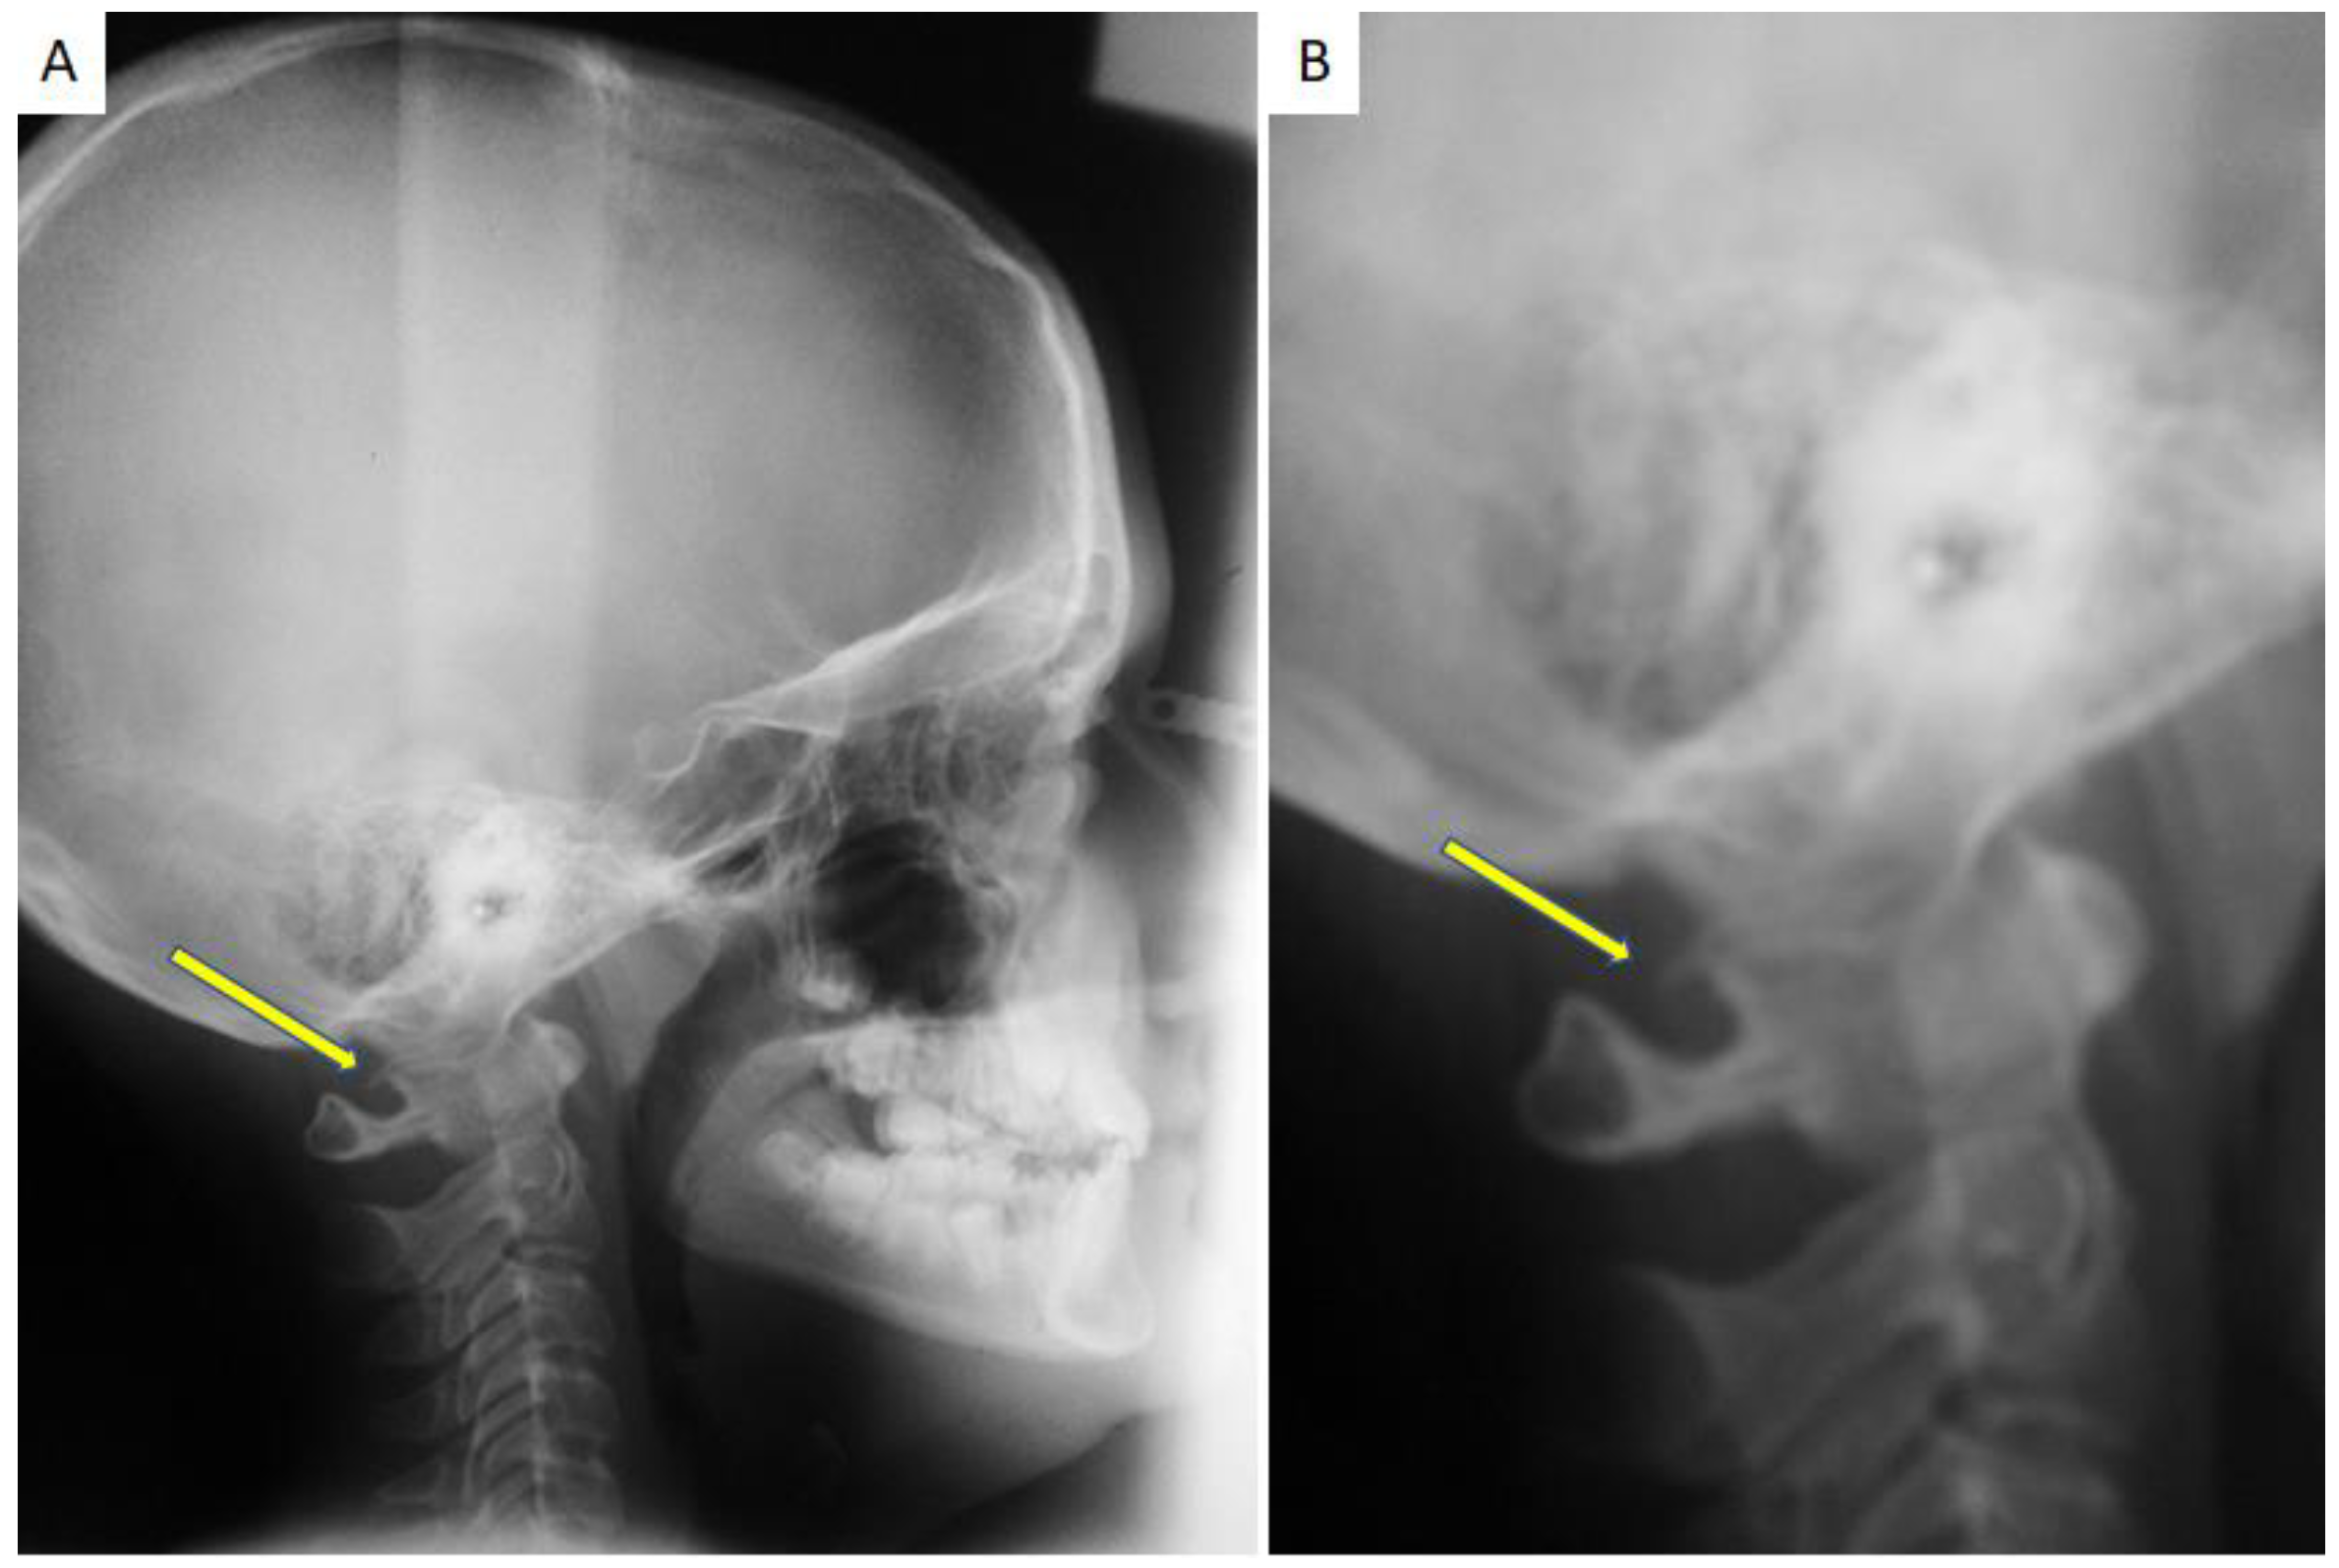

Calcification of the Atlanto-Occipital Ligament (Ponticulus Posticus) in Orthodontic Patients: A Retrospective Study